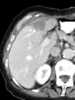

Metastatic ovarian cancer